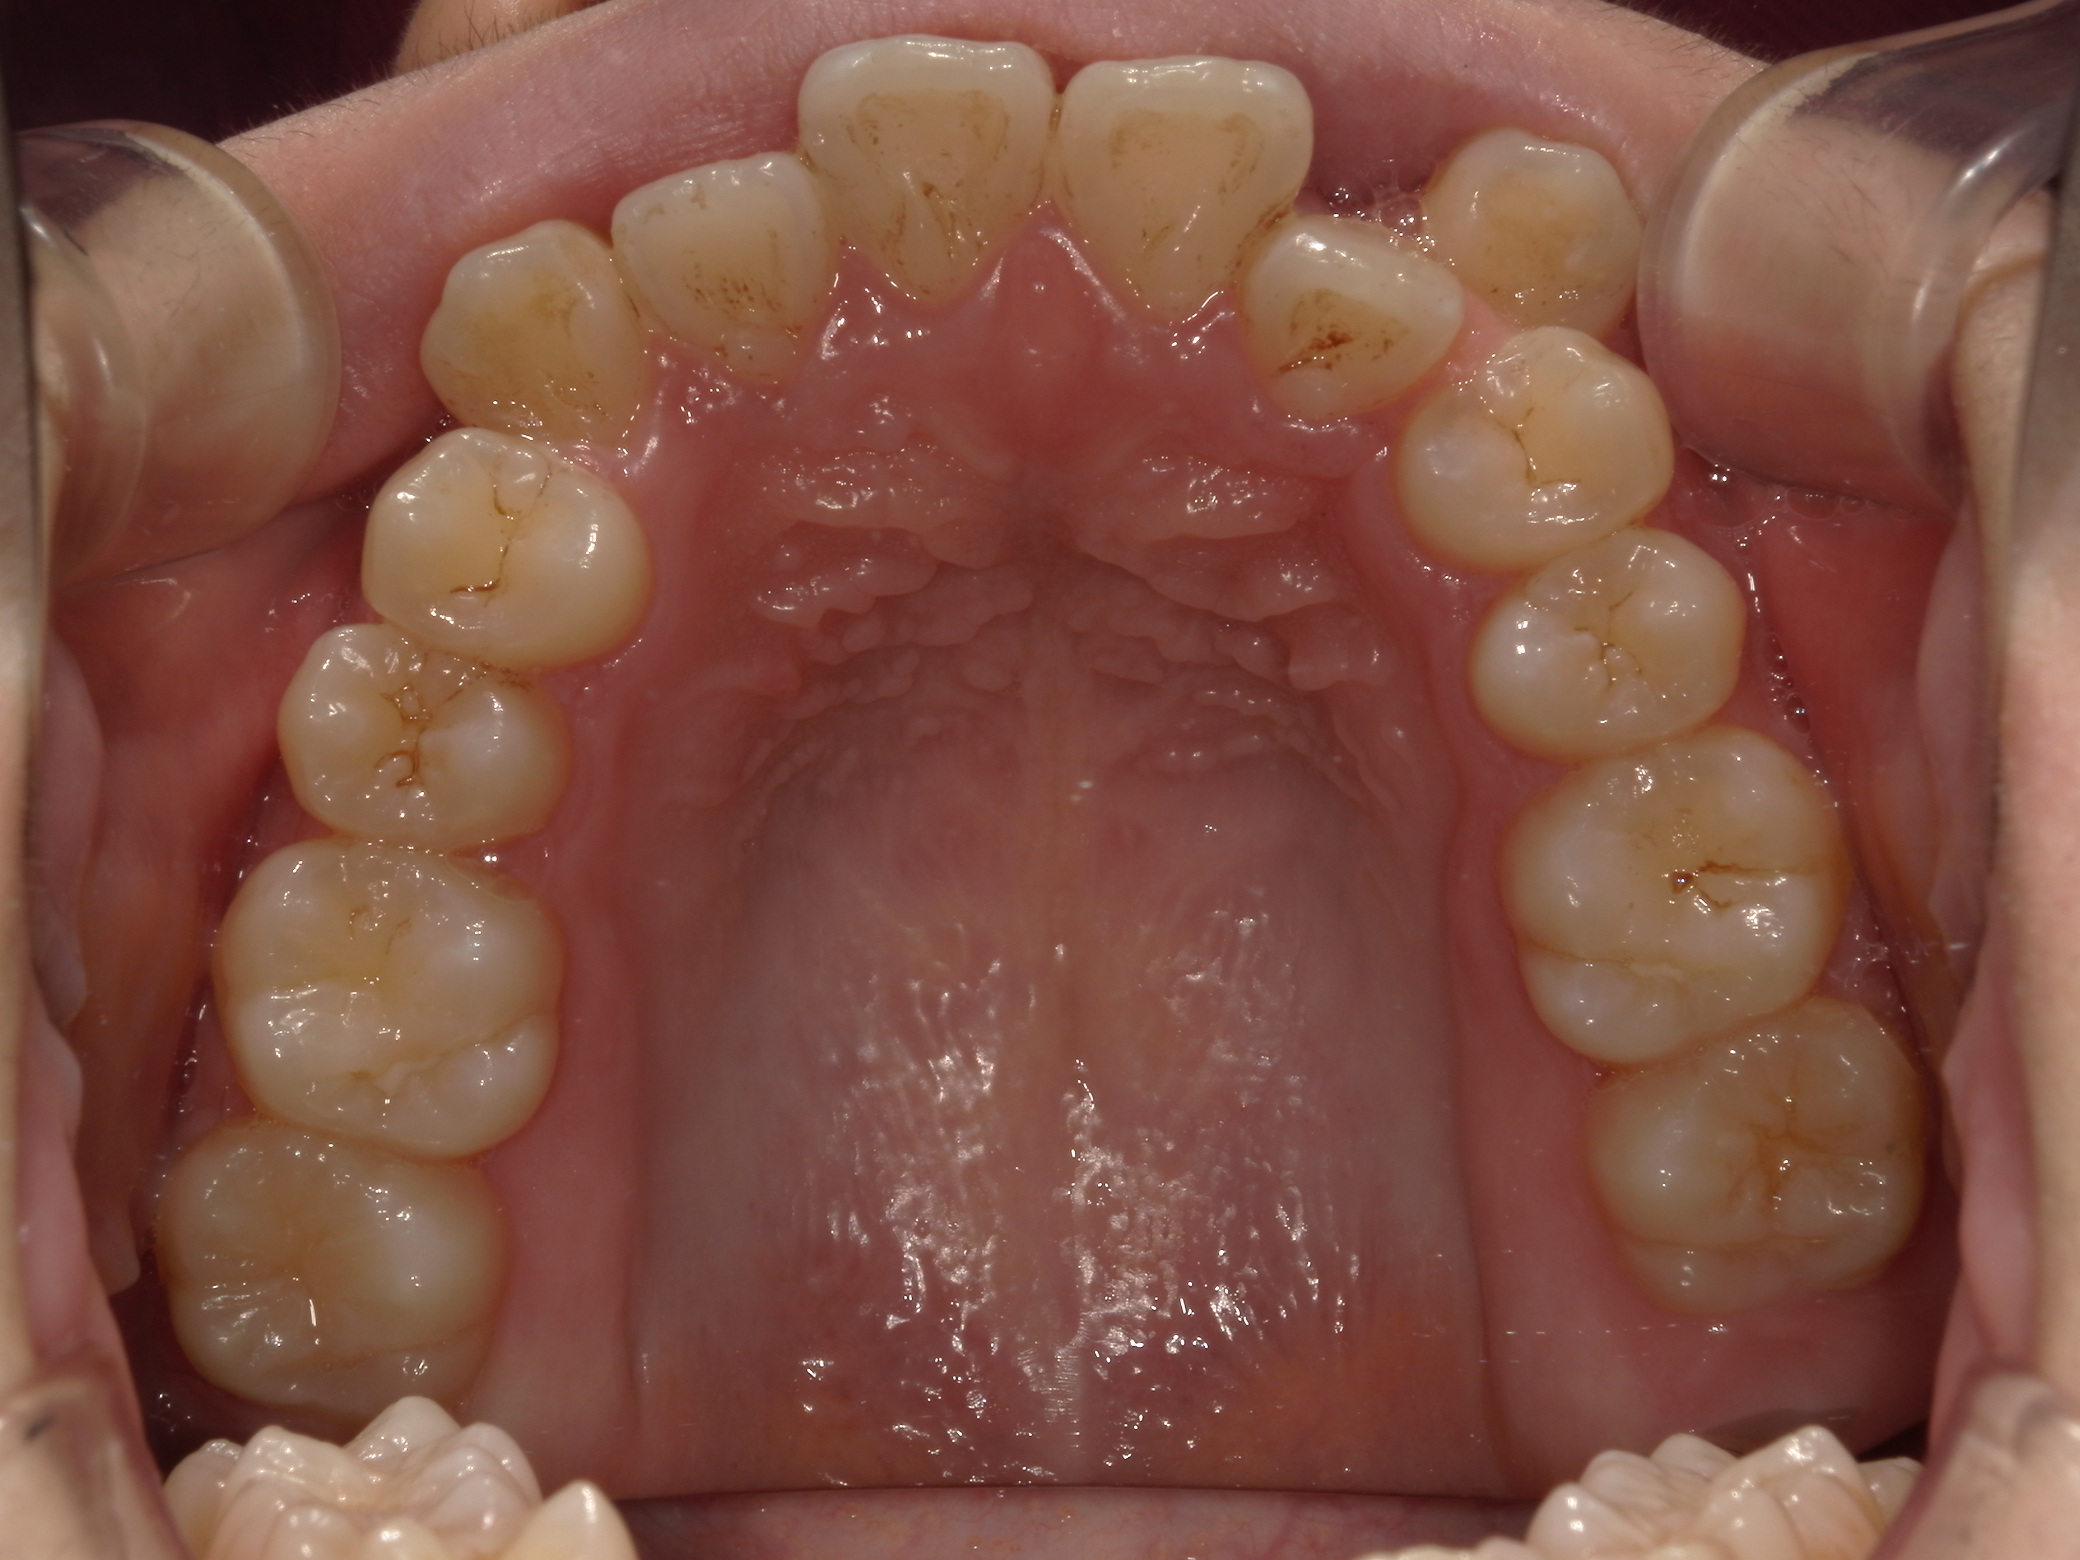

歯並びの乱れ(叢生)が気になる

| 年齢・性別 | – |

|---|---|

| 主訴 | 歯並びの乱れ(叢生)を気にされて来院された。咬み合わせや審美的な改善を希望されていました。 |

| 治療期間・回数 | 3年・28回 |

| 費用 | 840,000円 |